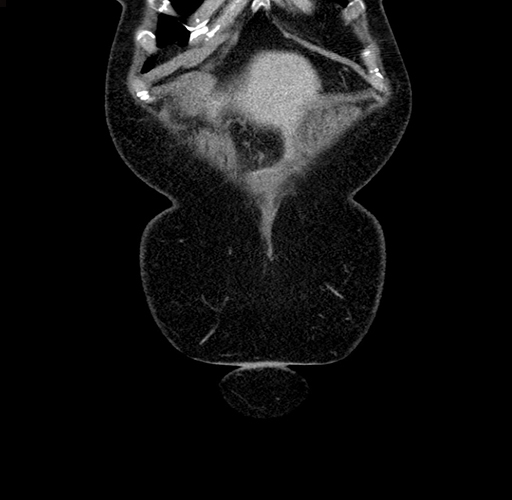

Pre-Chemo: Coronal Venous

Coronal Venous